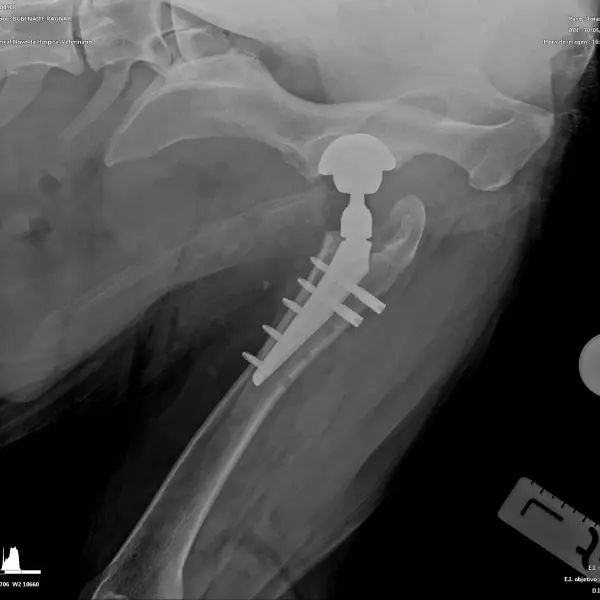

- Prótesis de cadera: es una técnica que generalmente se indica en pacientes adultos que padecen una enfermedad degenerativa articular (artrosis) avanzada. Consiste en la sustitución de los componentes acetabular y femoral afectados e involucrados en la articulación, por unos sintéticos, que permitirán una movilidad apropiada y sin dolor. Aunque es muy posible que un paciente necesite una prótesis en ambas caderas, nunca se realizarán de forma simultánea, espaciando las mismas el tiempo necesario para asegurar la recuperación de la primera. La mayoría de perros se encuentran bastante confortables pocos días después de la cirugía y vuelven a alcanzar niveles de actividad elevados unos meses más tarde.